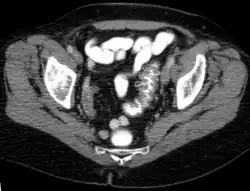

An Symptomen besteht ein plötzlich auftretender Schmerz über dem betroffenen Darmabschnitt am häufigsten im linken Unterbauch (deshalb auch Linksseiten-Appendizitis) oft mit Ausstrahlung in den Rücken und mit einer auf diesen Bereich begrenzten Peritonitis. Daneben sind häufige Symptome Fieber, Übelkeit, Erbrechen, eine Veränderung des Stuhlverhaltens von Durchfall bis Verstopfung mit Eiter und Schleim im Stuhl und Schwierigkeiten beim Wasserlassen, Dysurie genannt. In den Laborwerten fallen eine Erhöhung des CRPs und der Leukozyten auf. Teilweise kann bei der Untersuchung des Bauches des Betroffenen ein walzenförmiger Tumor (Tumor im Sinne einer raumfordernden Geschwulst) getastet werden. Die weitere Diagnostik erfolgt u. a. mit dem Ultraschall und einer CT-Untersuchung des Bauches. Bei der akuten Divertikulitis wird die Durchführung einer Darmspiegelung wegen des Risikos einer Perforation vermieden. Darmspiegelungen werden lediglich in Intervallen durchgeführt, um andere – insbesondere bösartige – Erkrankungen auszuschließen.[8]